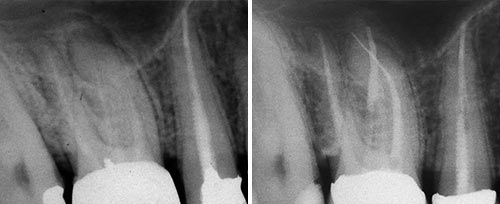

Peri-implant Mucositis

Courtesy of: Bogdan Crisan, DMD, PhD

Laser source: TwinLight®: Nd:YAG (1064 nm) + Er:YAG (2940 nm)

Peri-implantitis

Courtesy of: Aslan Gokbuget, DDS, PhD